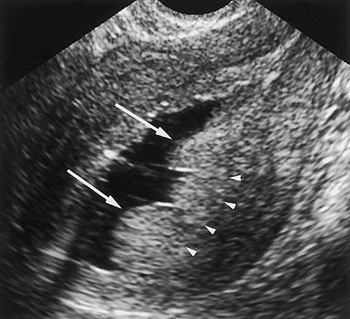

Затем проводится осмотр, чаще всего с использованием кольпоскопии. Этот метод позволяет оценить общее состояние репродуктивной системы женщины. После этого назначается ультразвуковое исследование, в ходе которого определяется степень увеличения эндометрия.